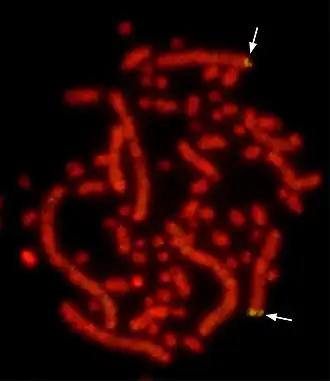

Флуоресце́нтная гибридиза́ция in situ, или метод FISH (англ. fluorescence in situ hybridization — FISH), — цитогенетический метод, который применяют для детекции и определения положения специфической последовательности ДНК на метафазных хромосомах или в интерфазных ядрах in situ. Кроме того, FISH используют для выявления специфических мРНК в образце ткани. В последнем случае метод FISH позволяет установить пространственно-временные особенности экспрессии генов в клетках и тканях.

Метод FISH используют в преимплантационной, пренатальной и постнатальной генетической диагностике[1], в диагностике онкологических заболеваний[2], в ретроспективной биологической дозиметрии[3].

Визуализацию связавшихся ДНК-зондов проводят при помощи флуоресцентного микроскопа. Интенсивность флуоресцентного сигнала зависит от многих факторов — эффективности мечения зондом, типа зонда и типа флуоресцентного красителя.